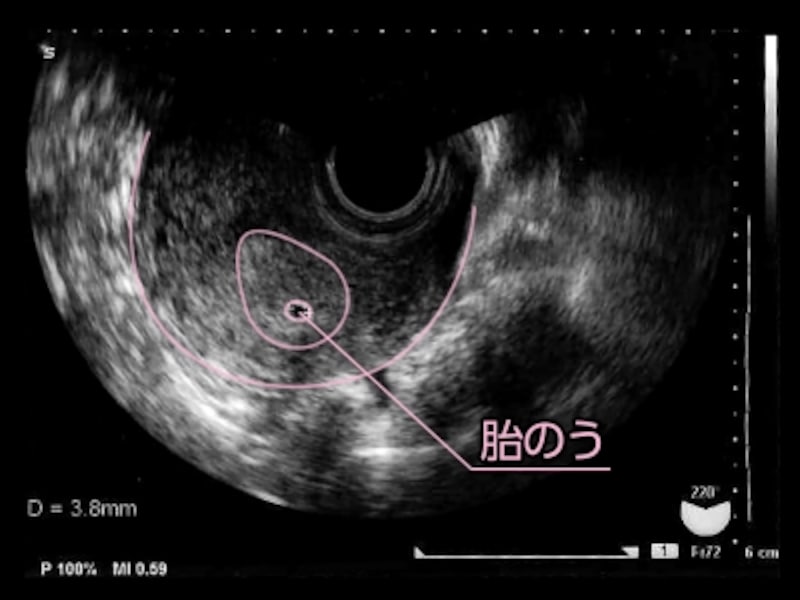

5 産科一般超音波検査 初期編 正常所見4 7週 日本産婦人科医会

5 産科一般超音波検査 初期編 正常所見4 7週 日本産婦人科医会

5 産科一般超音波検査 初期編 正常所見4 7週 日本産婦人科医会

5 産科一般超音波検査 初期編 正常所見4 7週 日本産婦人科医会

胎嚢 たいのう の大きさの平均は 妊娠5週 6週 7週の目安は 週数別に解説 ままのて